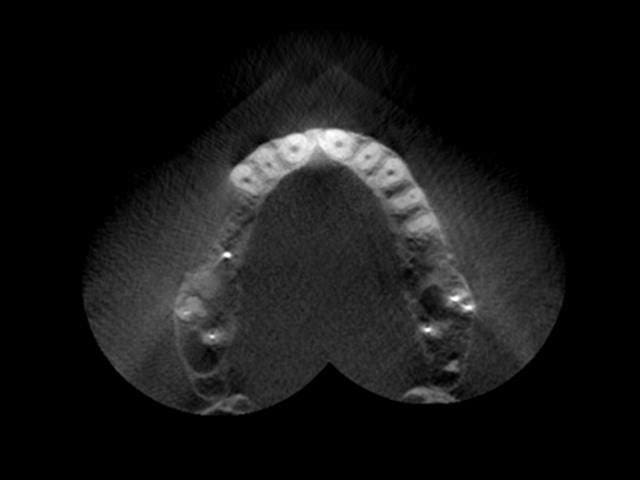

Les photos donnent la sensation que le manque est palatin mais c'est une illusion liée à la parallaxe.